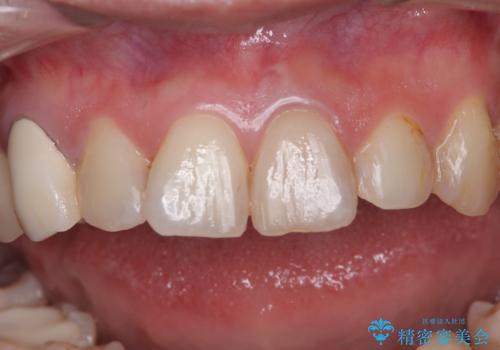

- むし歯により神経を取り除く処置をした歯と隣接する歯の捻れを気にして来院された患者様です。

神経を取り除いた歯は変色が始まっており、隣の歯は捻れにより突出している印象であったので、前歯2歯をオールセラミッククラウンにて補綴することとしました。

捻れている歯は、神経が露出する可能性があり、その場合には根管治療が必要となります。